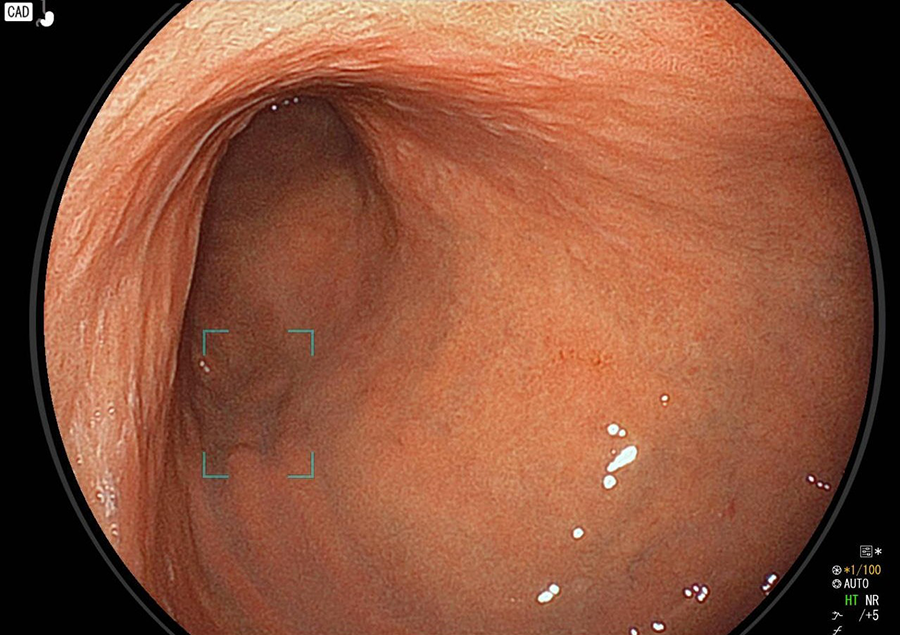

萎縮性胃炎

炎症が何年も持続すると、やがて胃粘膜が萎縮し、ひだまで消失します。胃粘膜の下の血管まで透けて見えてきます。